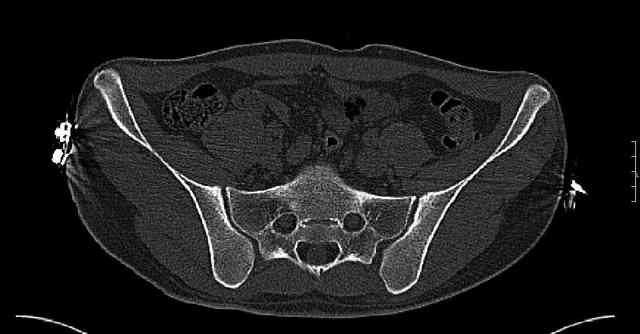

Some more images. Does it help to guess which part of the acetabulum is displaced?

Normal appearing SI joints and a healed posterior column limb... my bet's on caudal segment displacement.